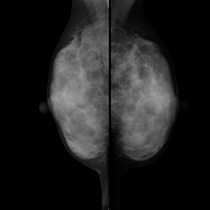

マンモグラフィ

マンモグラフィ(乳房専用X線撮影)では、微細な病変を画像化することができます。乳がんの早期発見のために重要な検査です。

マンモグラフィについて

乳房は、皮膚・脂肪・乳腺などにより構成された柔らかい組織です。その乳腺の中に存在する病変を捉えるために専用の装置(マンモグラフィ装置)で撮影します。 乳房を専用装置で出来る限り薄く均等に圧迫することにより、乳房全体を観察できるようになり、何より病変と正常組織の重なりが減り、病変の検出能が上がります。また、ボケを減らしたり、X線の量を減らすことができます。圧迫の際は最善の注意を払いながら行いますが、乳腺量(年齢や授乳経験の有無が影響)やホルモンのバランス(月経周期が影響)により、強い痛みを伴う場合もあります。月経開始7日~10日目くらいに検査を受けられることをお勧めします。